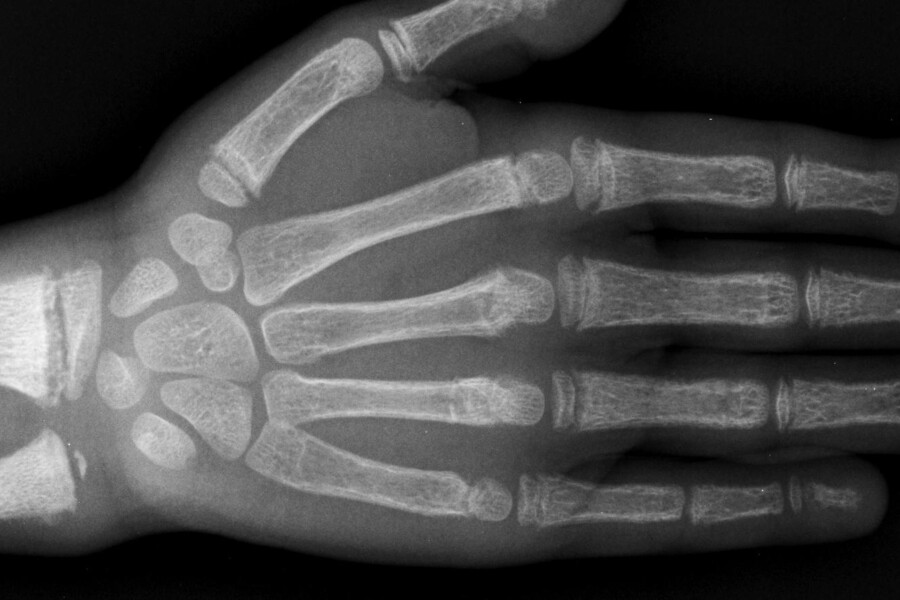

Kosti jsou velmi důležitou součástí našeho těla. Udržují nás ve vzpřímené poloze, podílejí se na pohybu a tvoří pevné pouzdro chránící naše nejcennější orgány jako je mozek, srdce a plíce. Na kostru jsou kladeny velké nároky po celý život. Podle toho, jestli jsme upoutáni na lůžko, anebo aktivně sportujeme, se kostra neustále přestavuje a přizpůsobuje našim potřebám. Pro tuto přestavbu a vůbec pro to, aby kost mohla fungovat tak, jak má, je nezbytný vápník a fosfor. Jen pro představu 99% vápníku v těle je uloženo v kostech. To, že se tyto prvky dostanou do kostí a jsou tam správně využity, je řízeno několika hormony a vitaminem D. Křivice je onemocnění vznikající v důsledku poruchy ukládání vápníku, fosforu a jiných prvků či jejich sloučenin do kostí. Kosti jsou typicky měkké a je porušena jejich přirozená přestavba, probíhající za normálních okolností celý život. Nemoc se projeví zpravidla u dětí ve věku od 6 měsíců do 3 let, kdy se kostra vyvíjí,a potřebuje tedy správný přísun potřebných látek. V podstatě rozlišujeme 2 typy křivice:

Vitamin D-rezistentní rachitida – jinými slovy křivice vznikající při normálním příjmu vitaminu D. Je jich několik typů a jsou často geneticky podmíněné (zděděné, vrozené). Obraz nemocného dítěte je podobný, ale vzhledem k tomu, že je to onemocnění vrozené, a tím dlouhodobé, postižení je většinou těžší. Vzniklá křivice je charakteristická kostmi s malým množstvím vápníku, jež jsou měkčí, což způsobuje jejich prohýbání, když dítě začíná chodit (nohy do O). S vývojem kostí blízce souvisí i vývoj zubů (také je důležitý vápník), takže zuby vyrůstají opožděně a mají poškozenou sklovinu. Hroutí se i obratle a dochází k různým zakřivením páteře